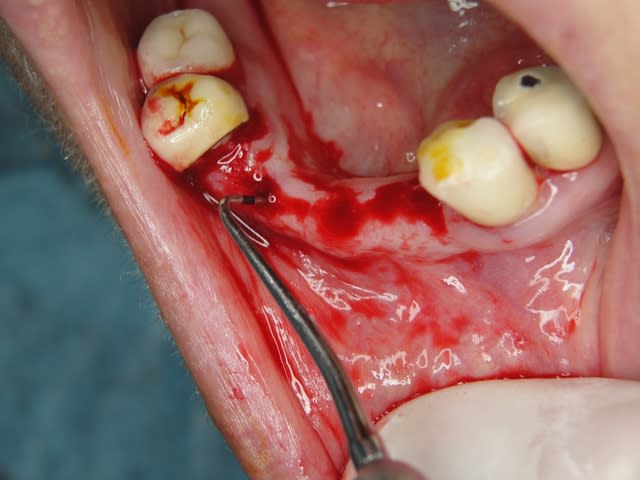

Maintenant concernant la demande de scans : je poste ce cas, une patiente vient me voir avec son scan car elle a consulté d'autres "spécialistes" et on lui refuse la pose d'implant secteur 4 où alors avec greffe préalable..Ca se discute..pas de temps à perdre je sais faire autrement..

Avec la chir trans gingivale technique MIMI ( Oui..un post sur la technique bientôt ..) j'ai pu placer deux 3,5/8mm..aurai je eu le meme résultat avec un lambeau..j'en doute..Les couronnes sont en titane. Recul clinique 2 ans ras. Simple efficace rapide moins onéreux satisfaisant pour le praticien et la patiente..